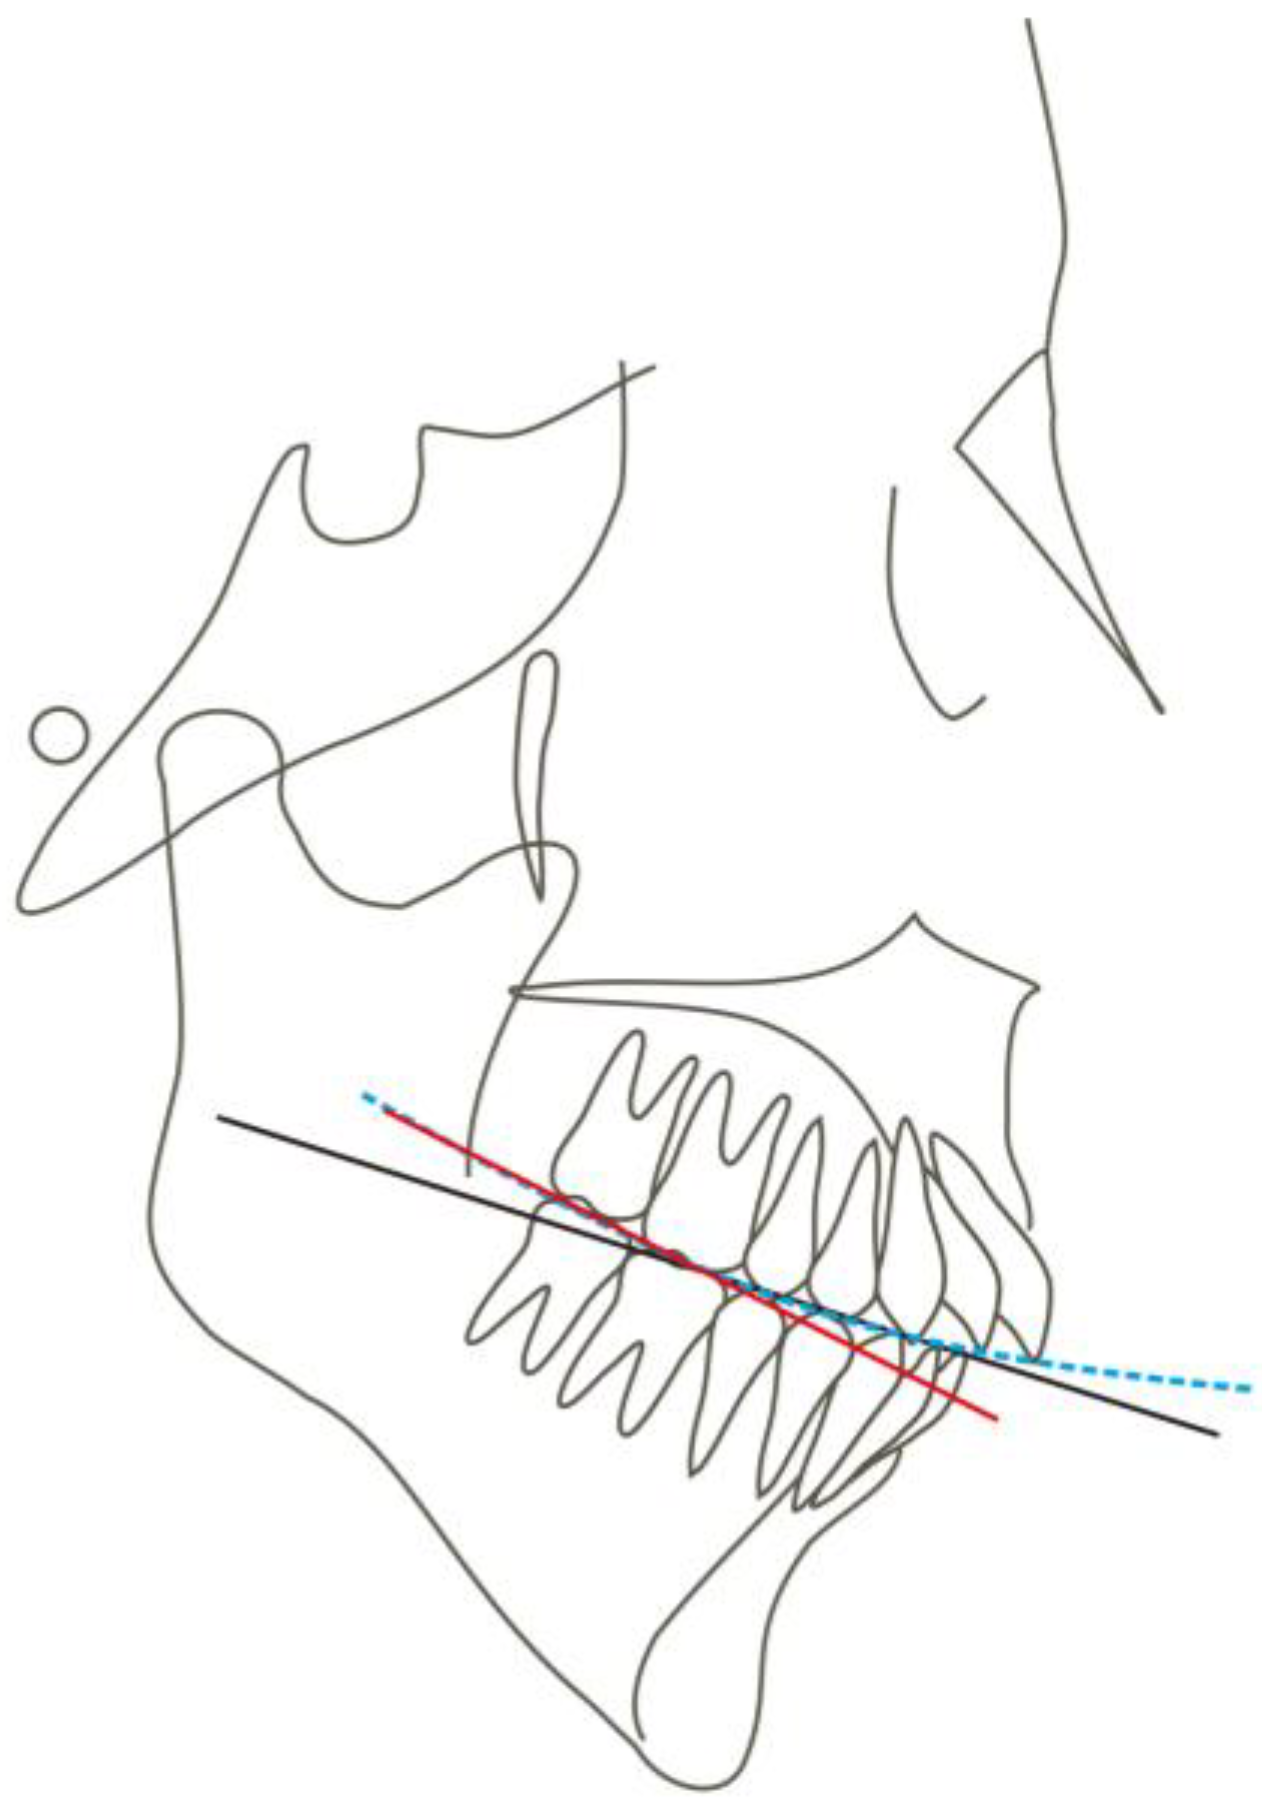

| Measurement | Normal Mean ± SD | Pretreatment | Posttreatment | Difference |

|---|---|---|---|---|

| SNA (°) | 83.1 ± 2.7 | 80.3 | 79.7 | −0.6 |

| SNB (°) | 80.3 ± 2.6 | 71.9 | 73.9 | 2 |

| ANB (°) | 2.7 ± 1.8 | 8.4 | 5.8 | −2.6 |

| UI-SN (°) | 103.4 ± 5.5 | 106.9 | 91.9 | −15 |

| LI-MP (°) | 96.3 ± 5.4 | 97.2 | 90.8 | −6.4 |

| UI-LI (°) | 129.1 ± 7.1 | 102.7 | 129.1 | 26.4 |

| MP-SN (°) | 32.6 ± 6.9 | 55.8 | 52.9 | −2.9 |

| MP-FH (°) | 25.5 ± 4.8 | 45.6 | 42.8 | −2.8 |

| Wits (mm) | −1 ± 1 | 5.8 | 2.8 | −3 |

| A-OP (°) | 10 ± 3.58 | 12.2 | 14.5 | 2.3 |

| P-OP (°) | 14.9 ± 3.85 | 25.1 | 16.2 | −8.9 |

| U1-PP (mm) | 28 ± 1.6 | 32.9 | 26.6 | −6.3 |

| U6-PP (mm) | 23 ± 1 | 24.4 | 19.3 | −5.1 |

| L1-MP (mm) | 40.8 ± 1.8 | 44.1 | 39.3 | −4.8 |

| L6-MP (mm) | 31.1 ± 1.9 | 33.4 | 28.9 | −4.5 |

| Palatal-OP (°) | 10 ± 4 | 17 | 15.7 | −1.3 |

| Upper Face Height (mm) | 50 ± 2.5 | 56.4 | 55.8 | −0.6 |

| Lower Face Height (mm) | 65 ± 4.5 | 81.1 | 75.4 | −5.7 |

| Anterior Face Height (mm) | 115 ± 5.5 | 135.9 | 130.8 | −5.1 |

| Posterior Face Height (mm) | 45 ± 5 | 75.9 | 73.2 | −2.7 |

| P-A Face Height (%) | 65 ± 4 | 55.8 | 56 | 0.2 |

| Y-Axis (°) | 67 ± 5.5 | 84.7° | 83.1 | −1.6 |

| UL-E (mm) | −1.6 ± 1.5 | 5 | −1 | −6 |

| LL-E (mm) | −0.2 ± 1.9 | 7 | −1.3 | −8.3 |